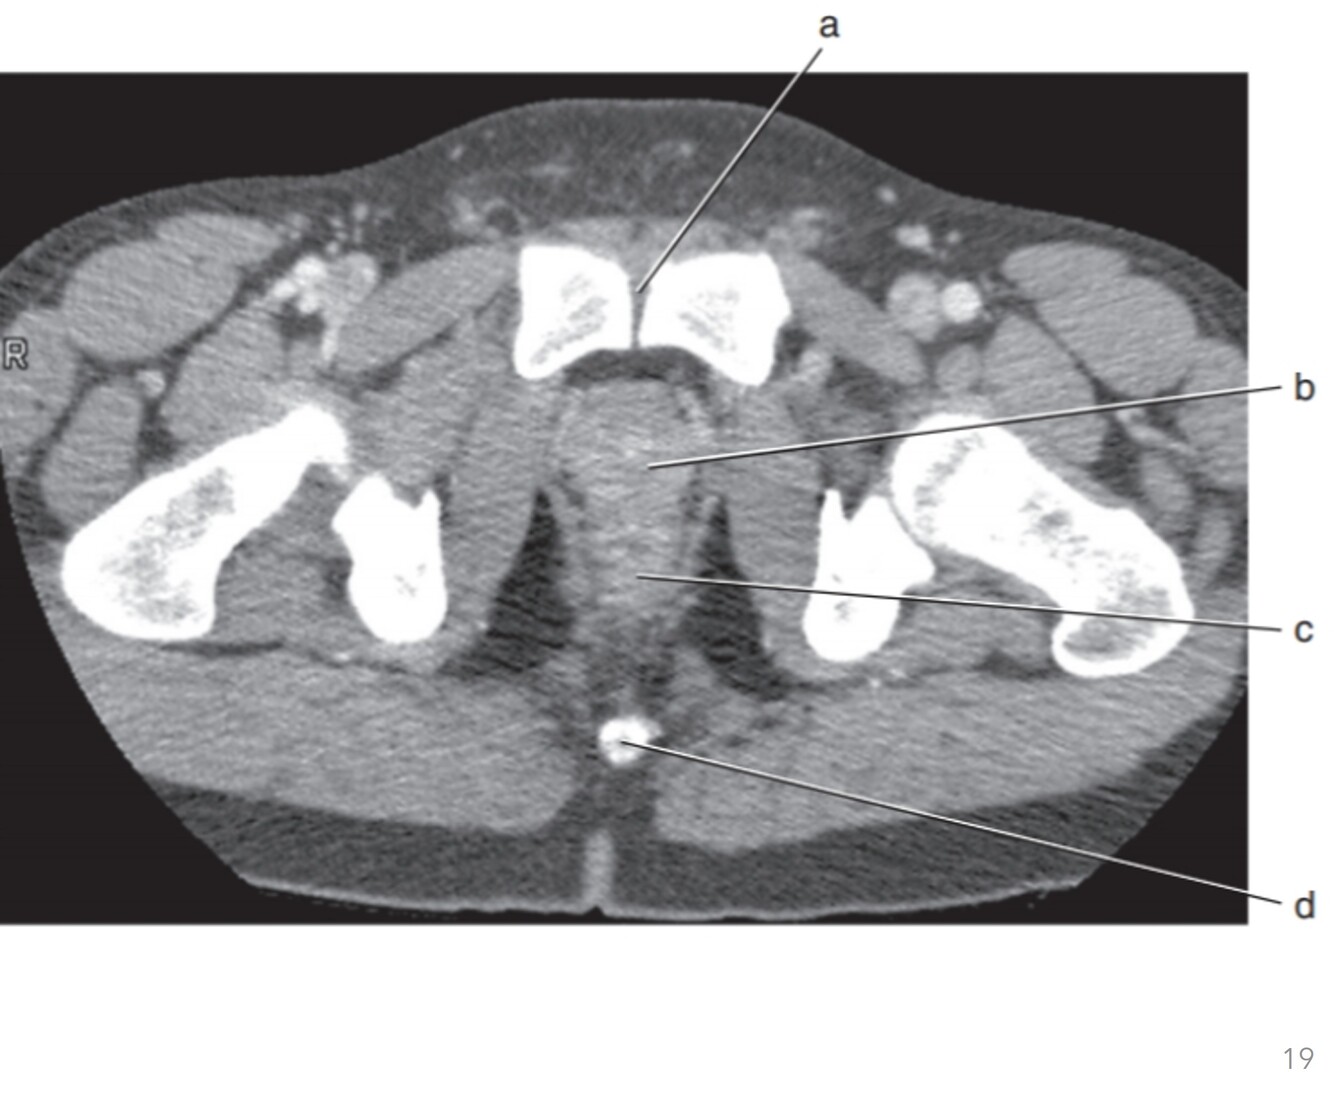

20

Q

Label a-d

A

a. Pubic symphysis

b. Prostate gland

c. Rectum

d. Coccyx